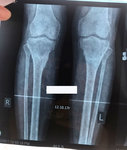

Исходник - 19 лет.

Дата операции 25.05.2017г.

58 дней.

Через 2 недели можно на снятие аппаратов.

Дата снятия аппаратов 10.08.2017г.

Срок лечения 75 дней.